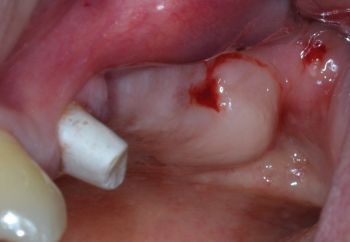

At four-weeks follow-up, both healing and soft tissue condition were considered satisfactory (Fig. 16).

Fig. 16: Four-week follow-up